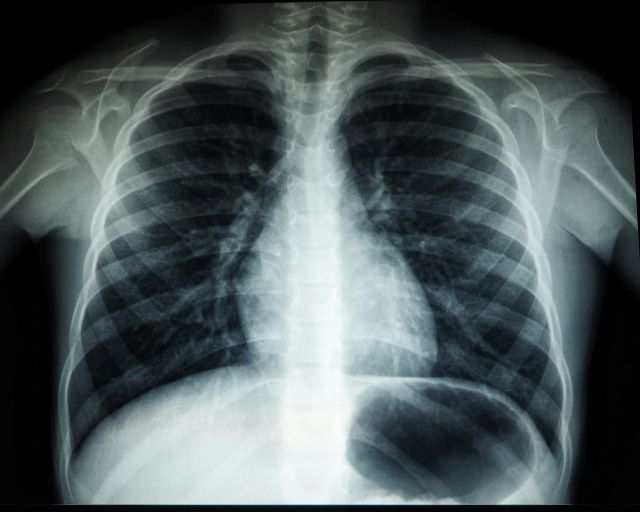

- Evaluating pathology and diagnostic findings

One of the most challenging aspects of environmental lung cancer cases is proving causation. Because lung cancer may result from multiple risk factors, courts require detailed medical and occupational analysis.

- Comparing occupational exposure levels to medical findings

- Evaluating exposure duration and concentration

- Reviewing epidemiological studies

- Assessing alternative contributing factors

Each case is highly fact-specific and requires structured expert evaluation.